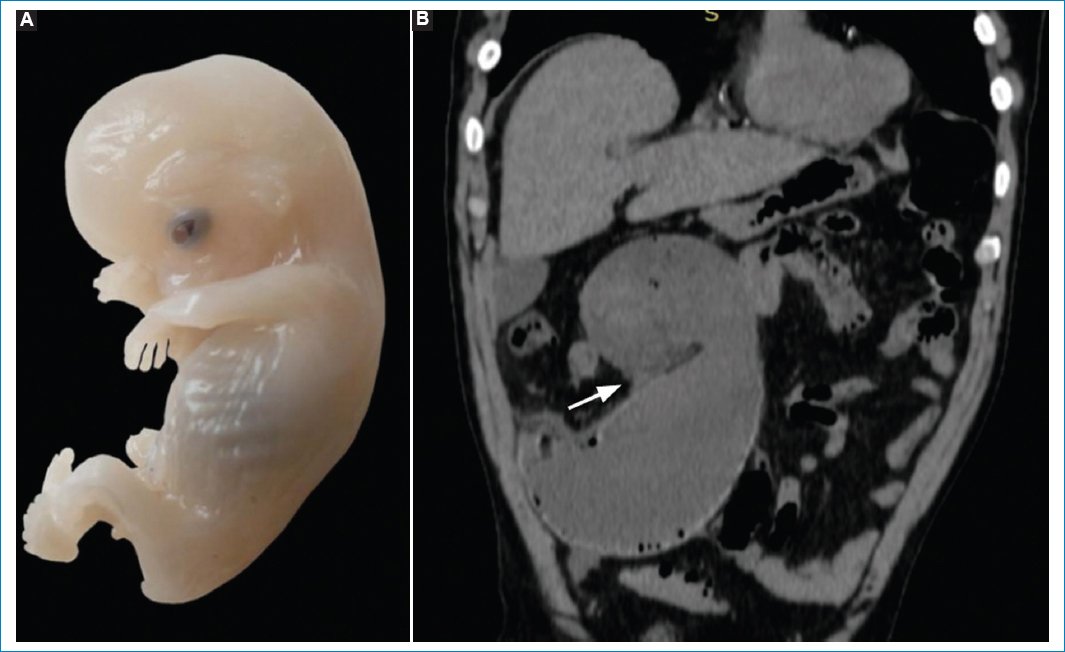

Figura 2. (A) Embrión humano de 8-9 semanas de gestación (imagen tomada de Wikimedia Commons, usuario Anatomist90, disponible en: https://commons.wikimedia.org/wiki/File:Human_embryo.jpg, bajo licencia CC BY-SA 4.0, con autorización). (B) TC abdominal con reconstrucción en plano coronal de paciente masculino de 67 años que acude a nuestra institución con dolor en fosa ilíaca derecha de 4 horas de evolución, sin otros síntomas acompañantes. Se evidencia al ciego distendido y volvulado con punto de torsión en válvula ileocecal (flecha blanca), e incipientes signos de neumatosis parietal.

Figura 3. Scout de TC abdominal del mismo paciente de la figura 2. Si bien el signo puede observarse en cualquier cuadrante abdominal, es importante distinguir la concavidad derecha del vólvulo junto con su segmentación haustral.